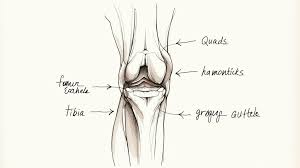

• 무릎까지 뻗는 통증 : 고관절 통증이 “무릎”으로 느껴지는 경우도 있어 위치만으로 단정하긴 어렵습니다.

• 움직임 제한 : 양반다리/다리 꼬기/양말 신기처럼 “회전” 동작이 특히 불편

고관절 통증은 “어디가 아픈지”보다 어떤 상황에서 아픈지(걷기, 회전, 누워있기, 아침 뻣뻣함)가 힌트가 되는 경우가 많습니다. 오늘 정리한 증상 패턴으로 내 통증을 한 번 분류해보시고, 체중 부하 불가·외상·발열 같은 위험 신호가 있거나, 2주 이상 지속된다면 진료로 원인을 확인해보시는 게 안전합니다.